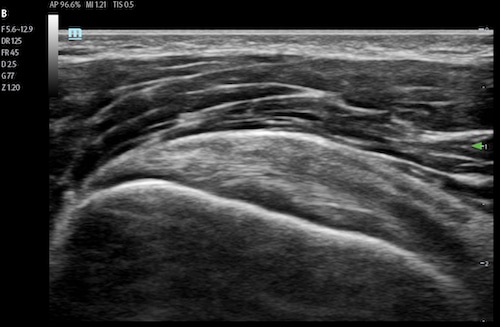

A linear transducer is a straight transducer. The linear transducer’s length determines the image’s sector width and shape. A linear transducer offers detailed resolution at superficial depths. Linear transducers are most frequently used with MSK, nerve, small parts, vascular, and pediatric applications.

Supraspinatus visualized with a linear transducer